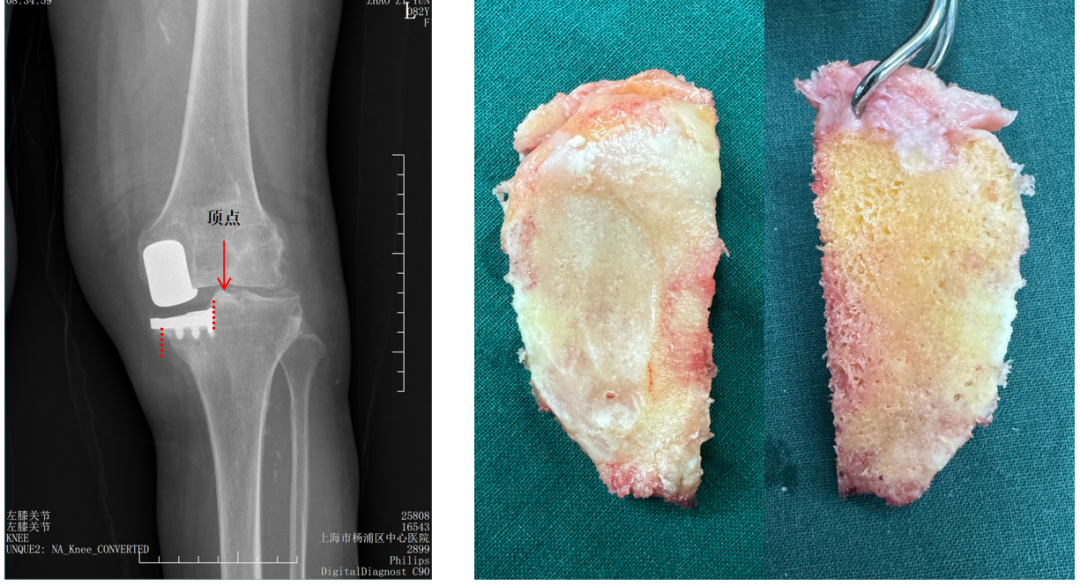

胫骨截骨宽度不足(距离顶点>2mm)

胫骨截骨跨越顶点